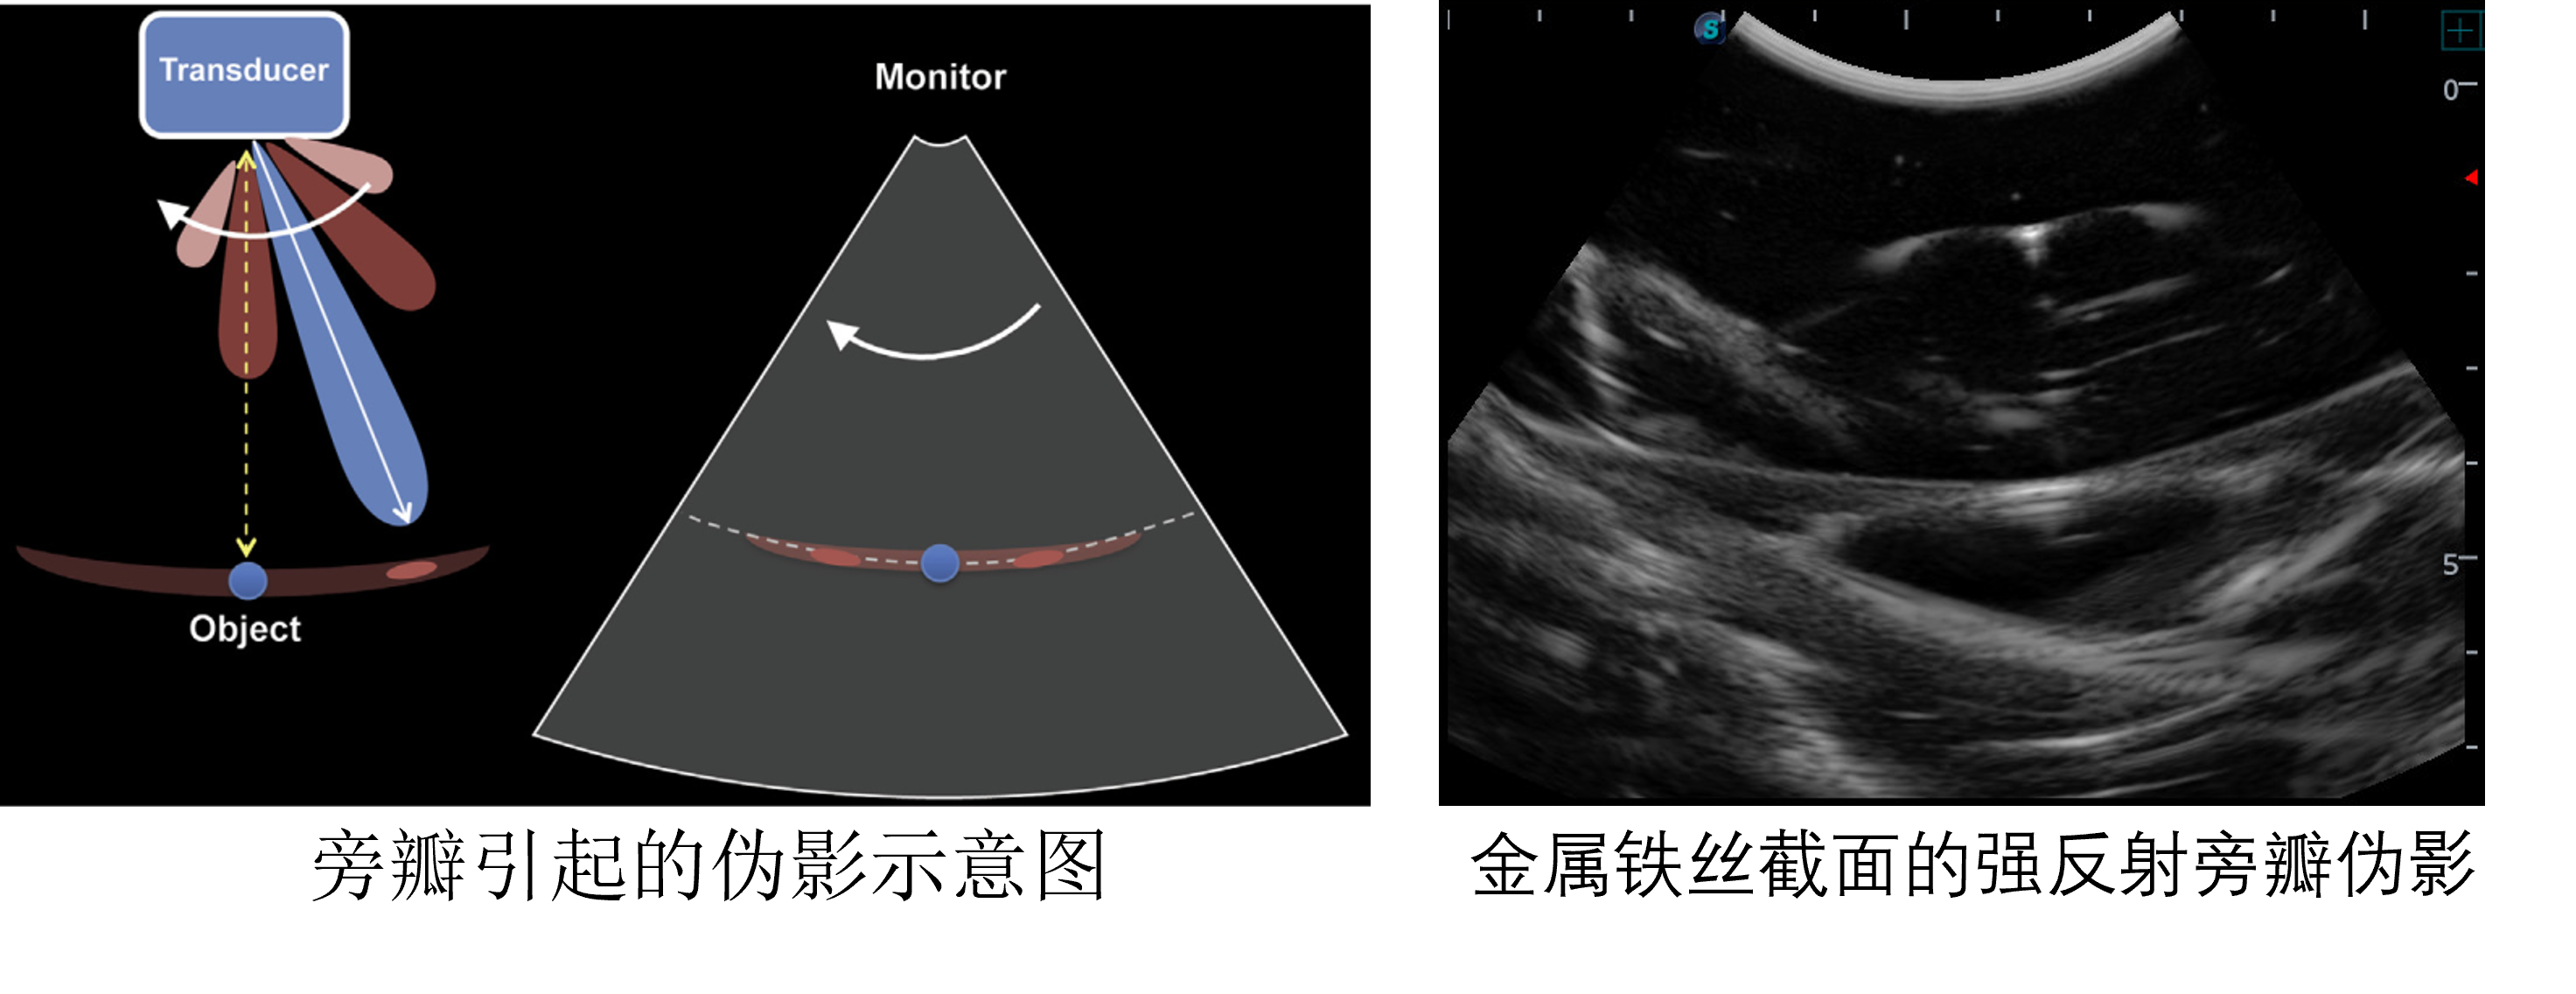

- 所有回声信号默认来自声束中轴(旁瓣伪影的成因)

旁瓣伪影

如果旁瓣的能量够强,能够成像,但是默认只有主瓣成像,那么在主瓣当前方向就会产生伪影